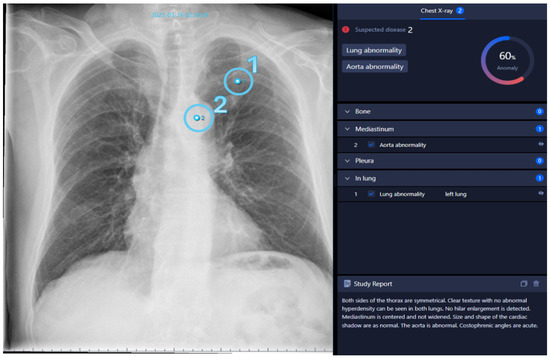

3.4.1. Fractures

A frequent mistake made by the AI is interpreting the joint surfaces of the shoulder depicted in different projections, as well as projections of the scapula onto the thorax, as fracture lines due to their alignment with the thorax. False positive findings can also occur because of the superimposition of bones with foreign material, such as catheters.

On the other hand, vertebral fractures are most often overlooked by the AI because these are best assessed in the lateral view, whereas the software only takes the PA view into account. Examples of false positive and negative osseous findings are shown in Figure 5.

All in all, thoracic fractures are a subset of pathologies which are often overlooked by radiologists (see Figure 5D), who rather turn their attention to lung pathologies—a fact which is substantiated by our results showing a high number of fractures detected by AI alongside a low agreement with the human rater (see Figure 3).

Figure 5. Inconsistencies of fracture diagnoses: (A)—false-positive fracture of the right clavicle described by AI at the overlay of the clavicle and 2nd rib (pneumonia in the left basal lung was correctly identified); (B)—false-positive fracture description of the 10th rib on the right by AI due to overlay of external oxygen hose; (C)—false-negative bone status; fracture of the left clavicle was not described by AI (Note: other finding incorrectly labelling “aortic abnormality”); (D)—rib fracture on the right found by AI but overlooked by radiologists.